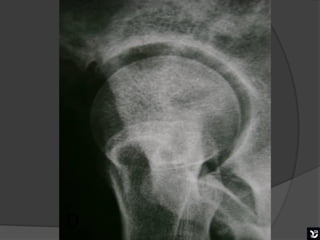

   Esta radiografia mostra bem uma boa mobilização na

incidência de Ducroquet. Podemos visualizar o colo

femoral bem alongado, trocanter menor visível em

perfil internamente.

PERFIL CIRÚRGICO DE ARCELIN

( CROSS TABLE)

   Posição supina com flexão do quadril contralateral e raio horizontal

e perpendicular ao colo femoral e ao filme, incidindo á face interna

da raiz da coxa que se quer avaliar em um ângulo de 45°.

Assim como na incidência de Ducroquet, o colo

femoral é visto em perfil permitindo uma boa

avaliação do colo e da porção anterior da transição

cabeça colo femoral.

Esta radiografia mostra bem uma boa mobilização na incidência de Ducroquet. Podemos visualizar o colo femoral bem alongado, trocanter menor visível em perfil internamente. Boa mobilização

PERFIL CIRÚRGICO DEARCELIN ( CROSS TABLE)  Posição supina com flexão do quadril contralateral e raio horizontal e perpendicular ao colo femoral e ao filme, incidindo á face interna da raiz da coxa que se quer avaliar em um ângulo de 45°.

Assim como naincidência de Ducroquet, o colo femoral é visto em perfil permitindo uma boa avaliação do colo e da porção anterior da transição cabeça colo femoral.